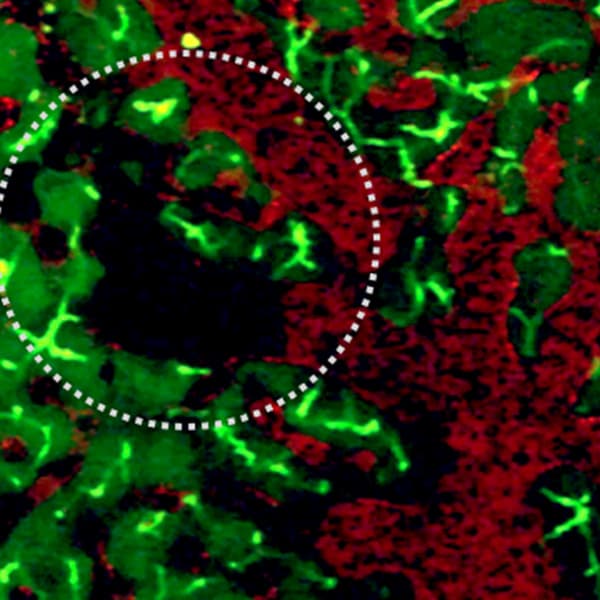

Intravital imaging of sickle cell mouse liver . In red Texas red dextran and Carboxyflurescein is in green. Circled area shows vasoocclusion.

Intravital imaging of sickle cell mouse liver. In red Texas red dextran and Carboxyflurescein is in green. Circled area shows vasoocclusion.